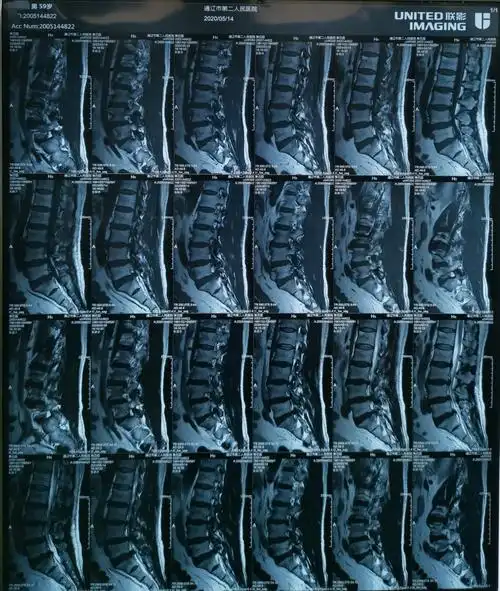

请谈谈对这例腰间盘突出症病人治疗的看法

在我院颈肩腰腿痛专科住院后,在c臂引导下进行了椎间孔镜微创手术治疗

病例分析 | 腰椎间盘突出症综合治疗

腰椎间盘突出,下肢胀麻.

椎间孔镜治疗腰椎间盘突出症

巨大腰椎间盘突出孔镜微创术 - 好大夫在线